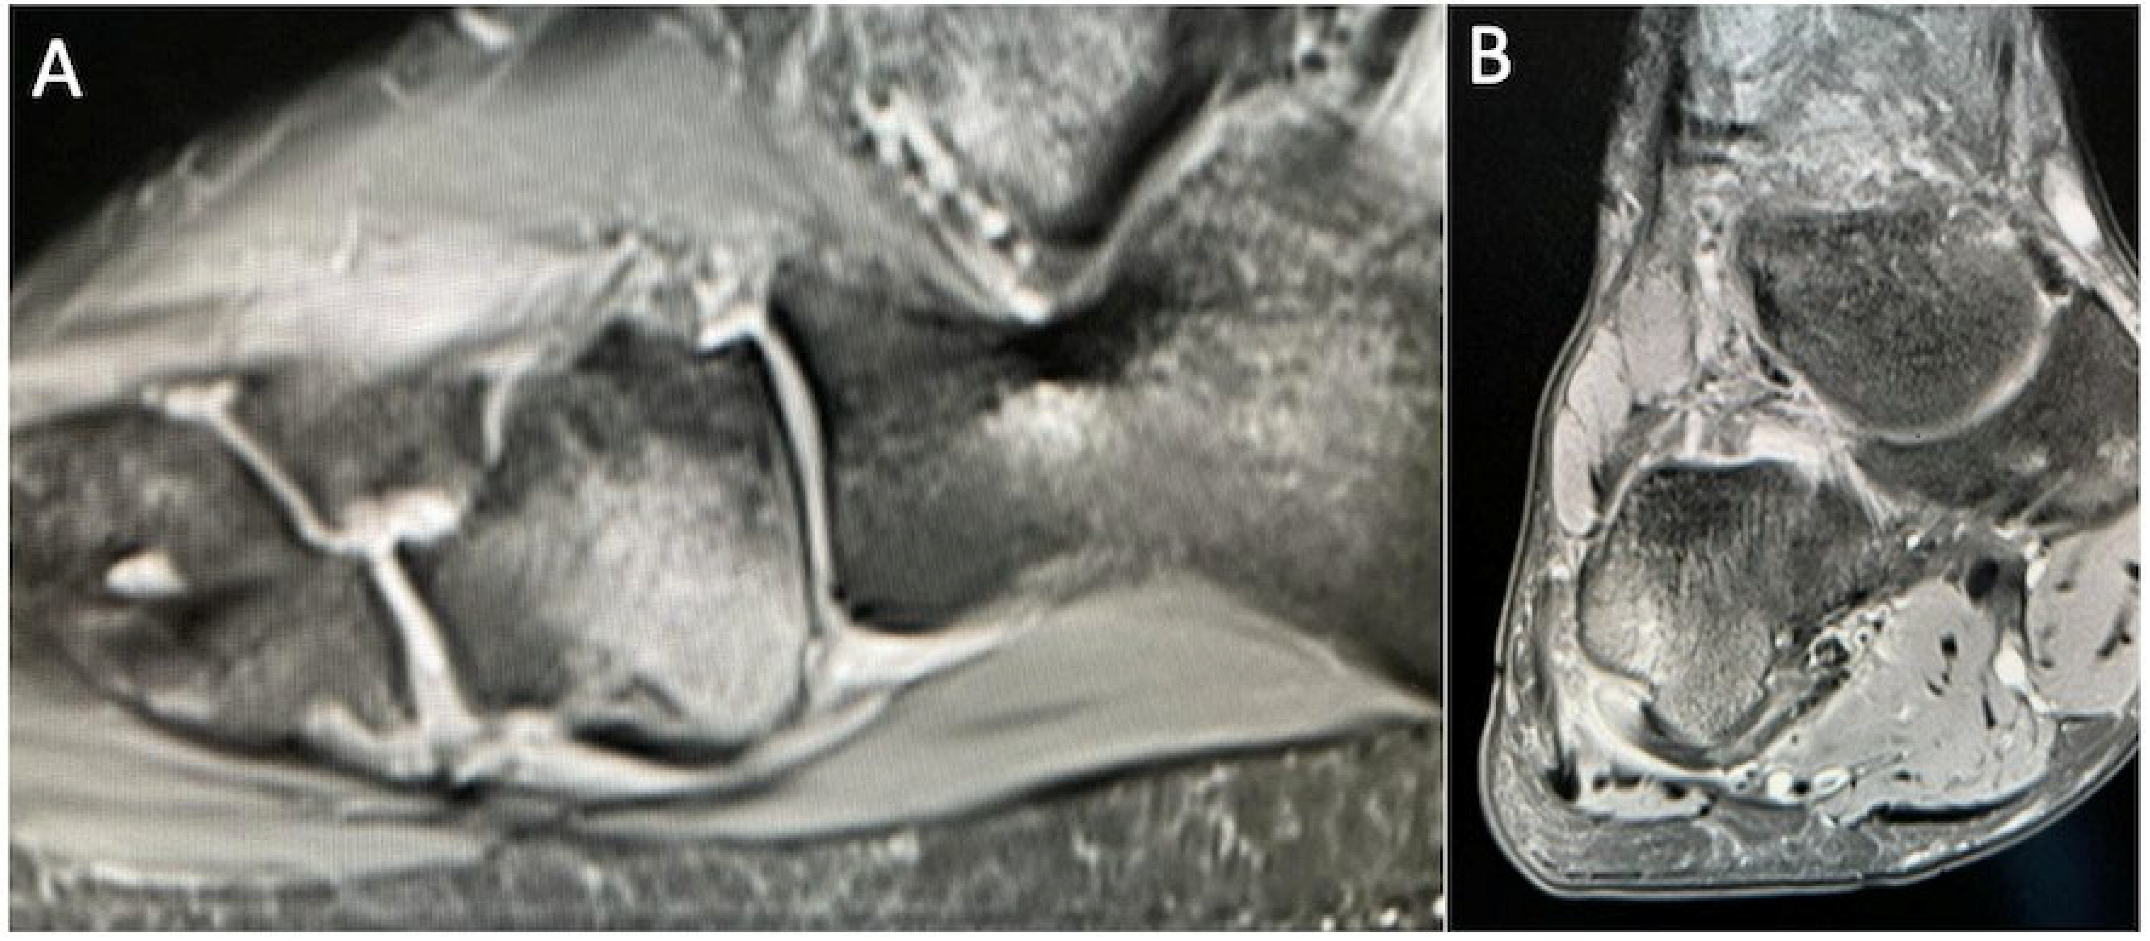

5.10. Gout